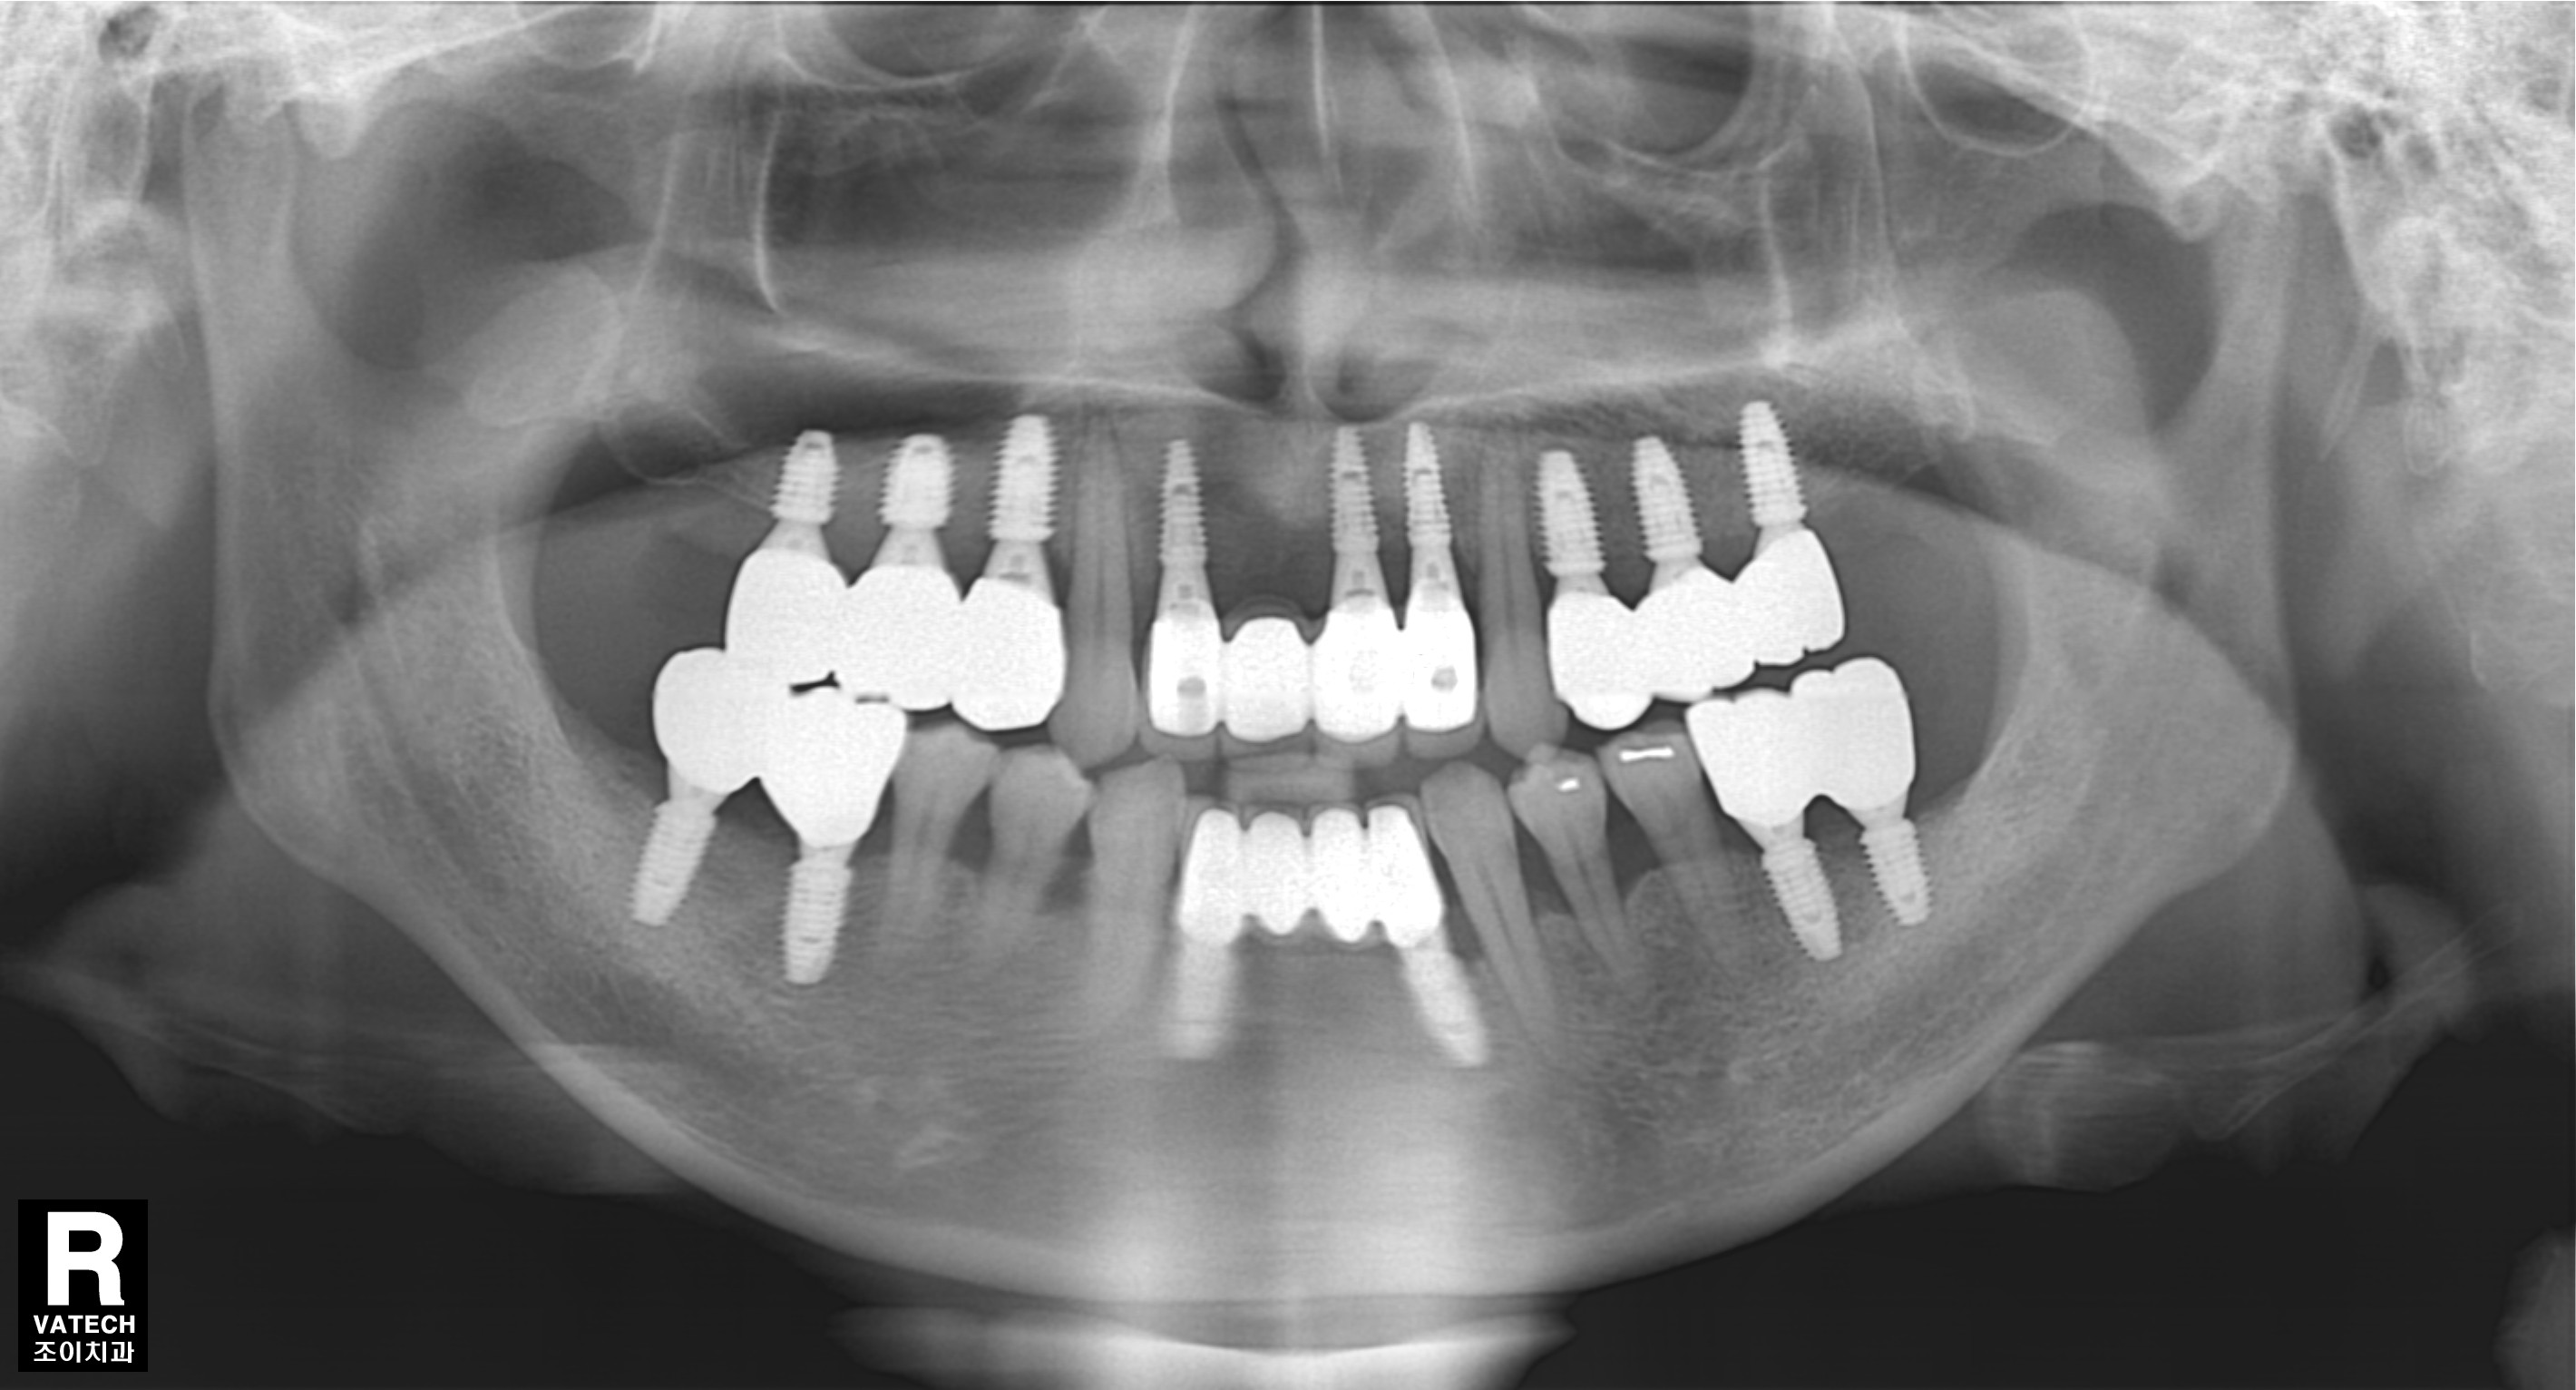

[임플란트] 제목 : 전반적 충치-치주질환에 이환된 젊은 환자의 치료

만일 현재처럼 임플란트와 충치치료를 할 수 없는 시대에 태어났다면, 그리고 젊은 나이에 치아가 모두 상한 경우라면 평생을 살아가는 데 삶의 질은 건치와 비교하여 정말 엄청난 차이가 있을 것 같습니다.

의학의 발전으로 자연치아와 거의 유사한 인공치아를 가질 수 있으니 참 좋은 일입니다.